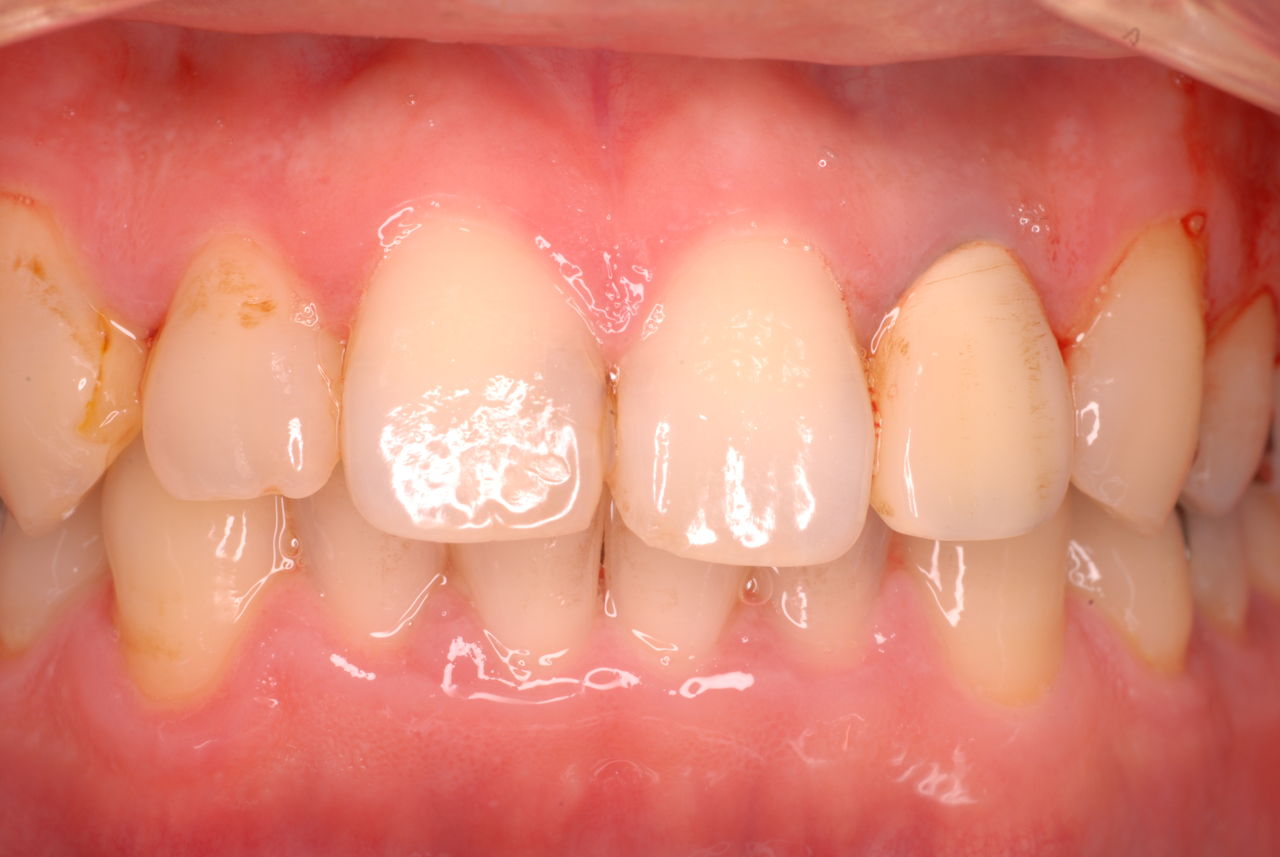

なかなかブラシの使い方ができていないようで、歯磨きと歯周病でのブラシの使い方は別なのですが、習ったことも検査もされずに金属を被せたりしているようで、これからも歯医者さんで抜かれたり、その後にインプラントのような高価な“クギ”を打ち込まれる方が増えるかと思うと残念です。

被せても、詰めても病気は治らないのですから。又病気の元になり易い不適合な差し歯や金属、インプラントがあればそこからバイキンが侵入して体に悪さもしやすいのではないかと心配しています。